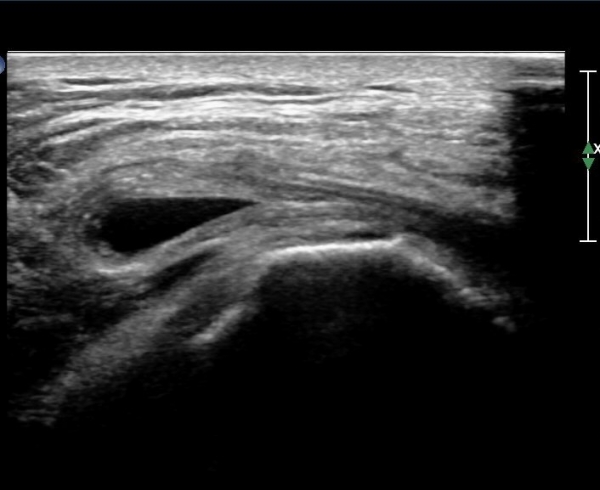

ŽÃËÀÚ¸¦ ¸Ó¸®ÂÊÀ¸·Î À̵¿ÇÏ´Ï ¼ö¾×Àú·ù°¡ ´õ ¸¹ÀÌ °üÂûµÈ´Ù(»çÁø 2, 3).